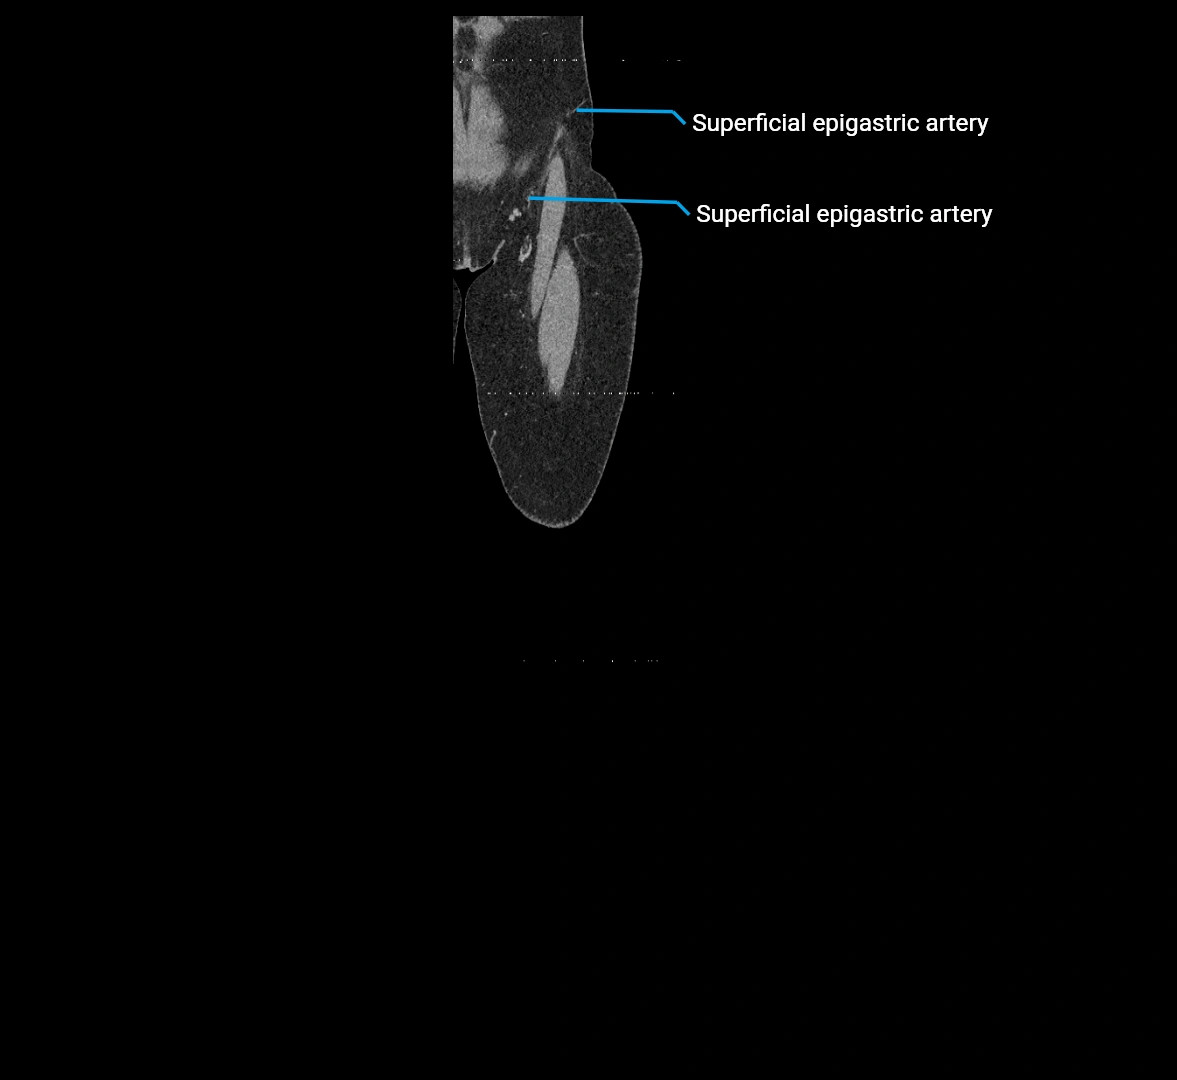

CT images

image

Contrast-enhanced CT (CTA):

• Gold standard for abdominal aortic imaging

• Provides excellent detail of lumen, wall, aneurysm, thrombus, and branch vessels

• Multiplanar and 3D reconstructions help in aneurysm measurement, stent graft planning, and dissection evaluation